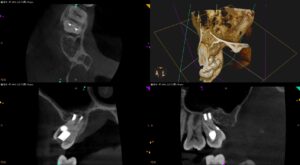

6段重ねの歯科治療その2〜#2 Ext→口腔外C処置→口腔外根管治療→口腔外支台築造→口腔外Apicoectomy→Intentional Replantation 1回法と1M recall

紹介患者さんの治療。 実は以前、紹介している患者さんのCaseである。 6段重ねの歯科治療その1〜#15 Ext→口腔外C処置→口腔外根管治療→口腔外支台築造→口腔外Apicoectomy→Intentional Rep … 続きを読む 6段重ねの歯科治療その2〜#2 Ext→口腔外C処置→口腔外根管治療→口腔外支台築造→口腔外Apicoectomy→Intentional Replantation 1回法と1M recall